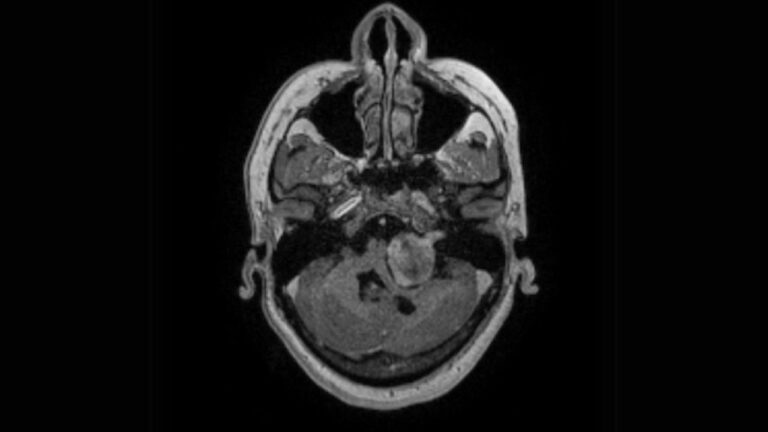

Os meningiomas são tumores que se originam das meninges, as membranas que envolvem o cérebro e a medula espinhal. Embora a…